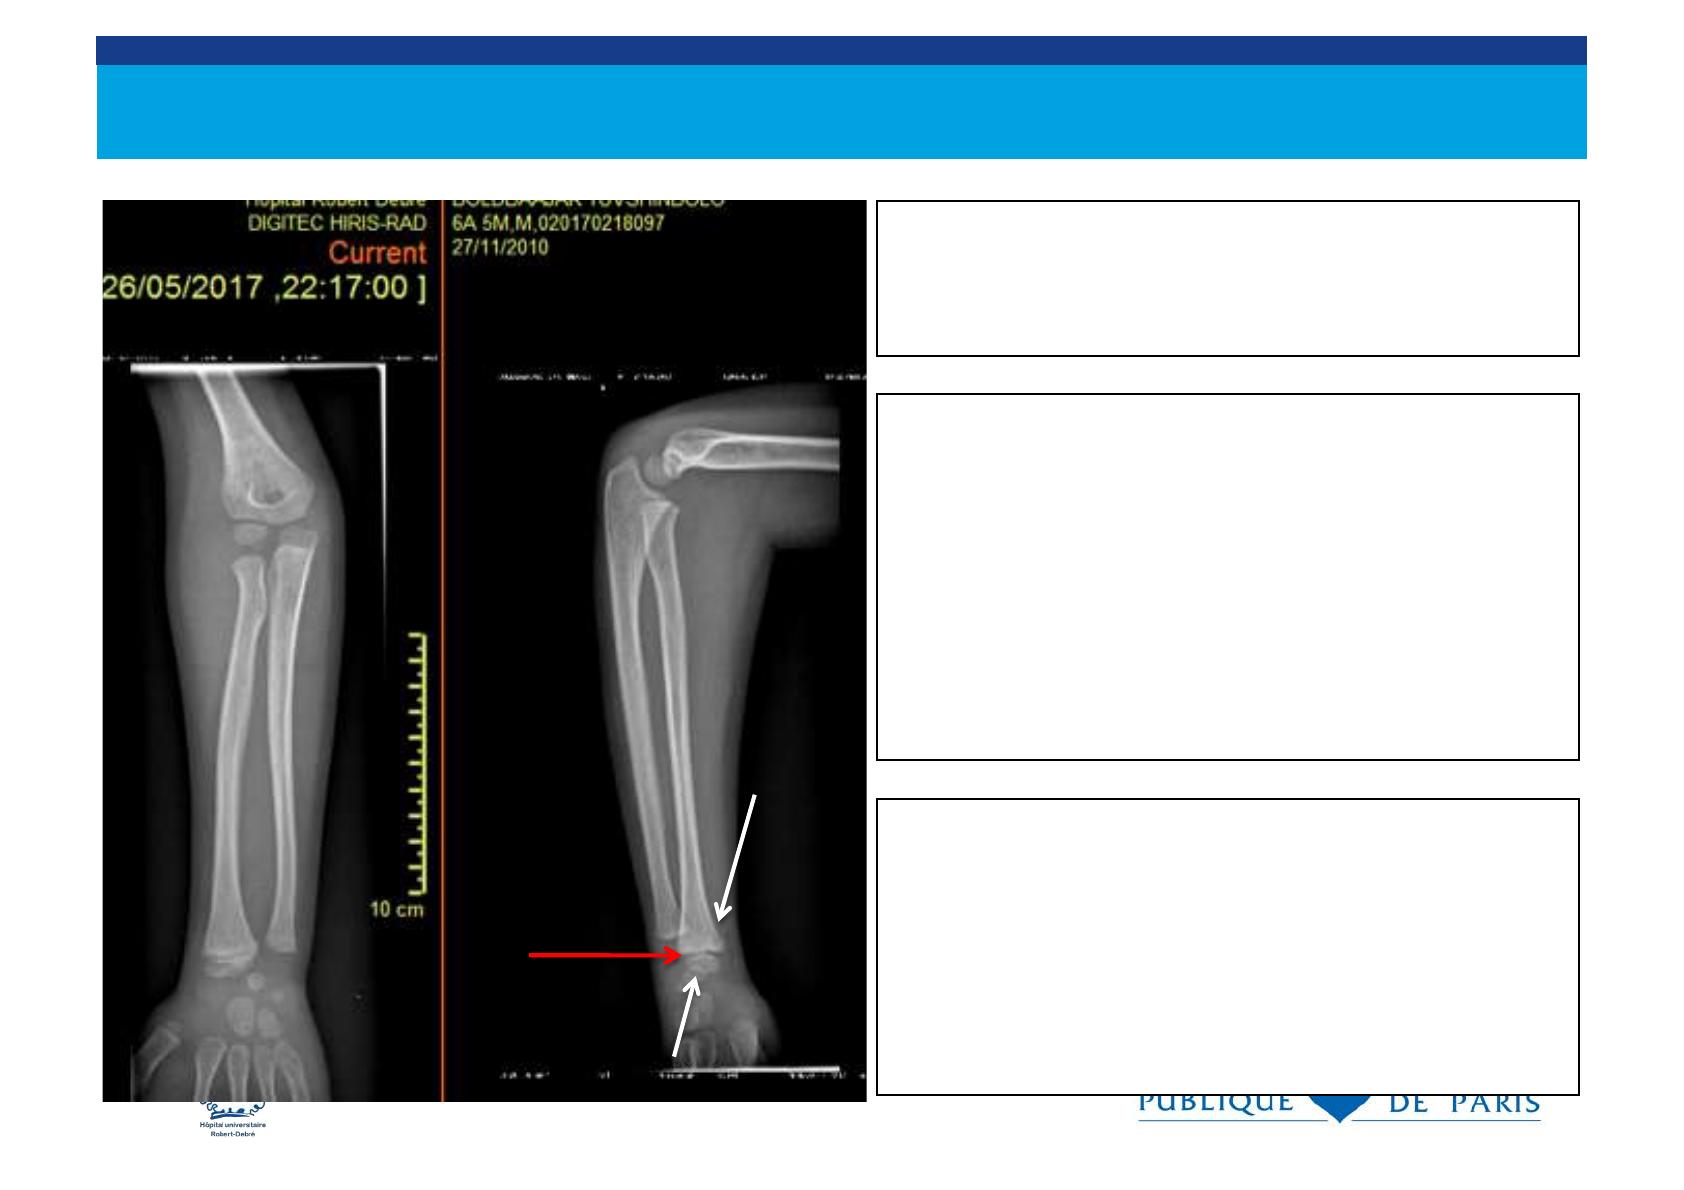

Le cartilage de croissance

. sépare l’ épiphyse de la métaphyse et il est

radiotransparent

. fragile et vulnérable aux traumatismes

. les fractures peuvent traverser le cartilage de

croissance.

. Les traumatismes du cartilage de croissance

déterminent le pronostic des fractures de l’ enfant

métaphyse

épiphyse

cartilage de croissance